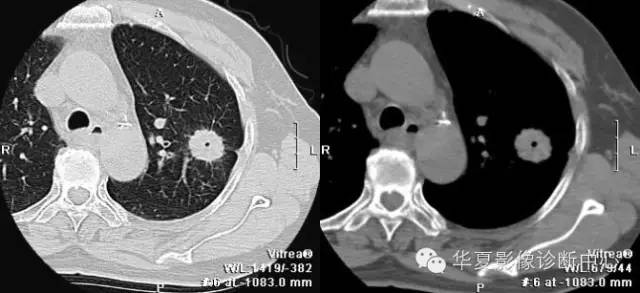

胸部高分辨扫描图像上,在肺野周边部或外1/3的肺内小叶间隔表现为不规则、结节状增厚。这是肿瘤细胞在毛细血管或淋巴管内不规则膨胀性生长以及继发的血管周围和间质水肿及纤维化。串珠样间隔征的形成,主要是转移瘤细胞或瘤栓经血型或淋巴播散以及逆行性淋巴管转移在肺周边部的毛细血管或淋巴管内,致使转移灶远测血管或淋巴管扩张;转移灶阻塞引起肺间质水肿;病灶在毛细血管和淋巴管周围不规则生长;长期间质水肿继发纤维增生;周边部毛细血管或淋巴管内肿瘤生长并填充其间。该征主要见于肺转移瘤,其次也见于肺结节病和先天性肺小叶周围纤维化。

肺转移瘤CT检查时,肺间质显示重要改变即间隔不规则增厚和串珠样改变,尤其在肺高分辨CT图像上,在肺野周边部或外1/3的肺内小叶间隔表现为不规则、结节状增厚。并把这一表现称作“申珠样隔征”。这一表现的病理基础被认为是肿瘤细胞在毛细血管和淋巴管内生长及继发血管周围和间质水肿及纤维化所致。大体病理检查,在CT显示串珠样隔处可见肿瘤不规则伸展性生长及周围毛细管和淋巴管的纤维化,镜检可见在肺泡间毛细管及淋巴管内和其周围有瘤细胞性小结节,病变远端有隔水肿、纤维化和血管扩张。 医学百科网 | YxBaike.Com

串珠样间隔征的形成,主要是转移瘤细胞或瘤栓经血型或淋巴播散以及逆行性淋巴管转移在肺周边部的毛细血管或淋巴管内,致使转移灶远测血管或淋巴管扩张;转移灶阻塞引起肺间质水肿;病灶在毛细血管和淋巴管周围不规则生长;长期间质水肿继发纤维增生;周边部毛细血管或淋巴管内肿瘤生长并填充其间。

肺内结节的位置、大小和数目对诊断转移瘤缺乏特异性,然而串珠样隔征主要见于转移瘤,虽然肺水肿和纤维化中可见一些光滑增厚的隔。所以,这一表现是提示肺转移瘤的高度敏感指征,尤其是对小的转移瘤有独特价值。

该征主要见于肺转移瘤,其次也见于肺结节病和先天性肺小叶周围纤维化。